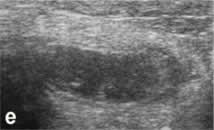

| д, е, ж - гангренозный (подтверждено на

операции) аппендицит у 8-летнего ребенка. Нарушена дифференцировка

слоев аппендикса, но при ротации датчика удается получить

структуру вытянутой формы, прилежащие к ней ткани гиперемированы

(отросток был окутан сальником). |